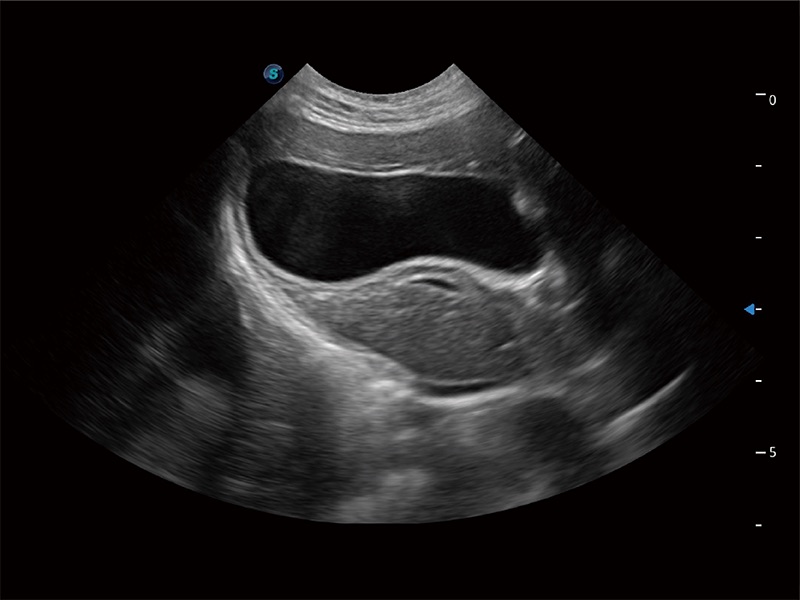

• Auto Bladder 膀胱自動測量

一鍵自動識別膀胱壁及自動測量膀胱容積,不受膀胱形狀和大小的限制,幫助醫(yī)生快速精準(zhǔn)獲得測量的數(shù)據(jù)。

(貓)膽囊